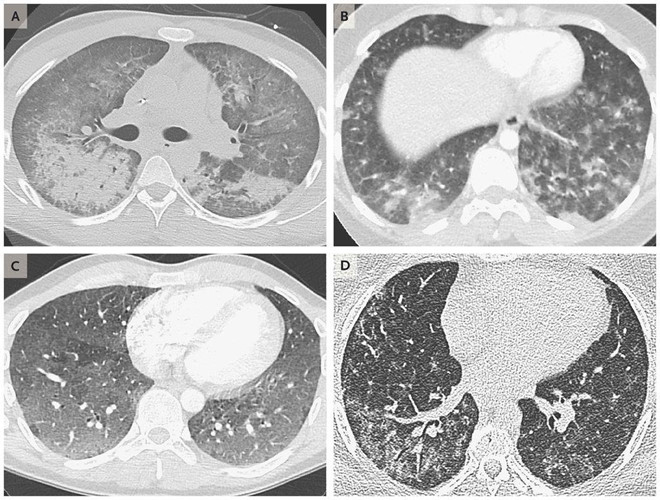

Hình ảnh scan phổi của 4 bệnh nhân tuổi từ 19 đến 49, cho thấy dấu hiệu tổn thương do sử dụng thuốc lá điện tử. Ảnh: New England Journal of Medicine.